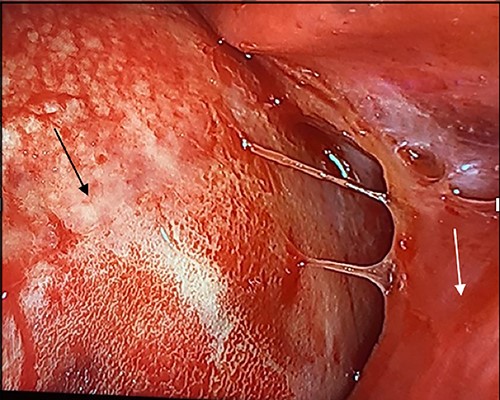

In the operating room, the patient was placed in the left lateral decubitus position exposing the right side of the chest. Upon entering the pleural cavity, a significant amount of bloody pleural fluid was seen. After fluid aspiration, the mediastinal mass was seen compressing the right lung (Fig. 3). Samples of the tumor were obtained and sent for frozen section analysis, which showed extensive necrosis and desmoplastic reaction, but no evidence of malignancy.

Intraoperative image with patient in left lateral decubitus position demonstrating the mass (black arrow) causing compression of the lung (white arrow).